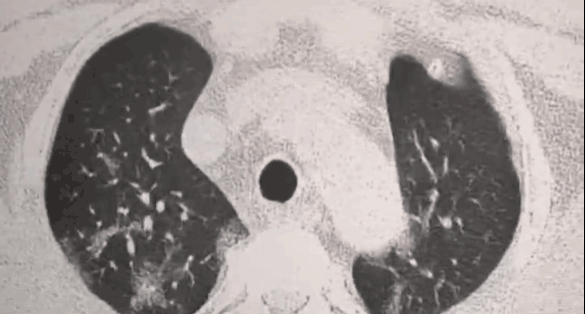

如果不加控制,就会发展成肺结节,肺纤维化,甚至肺癌,严重危及生命

数据显示,肺癌是恶性肿瘤死亡的第一杀手,每年肺癌病人约有80万人,死于肺癌的病人大约是65万,一旦染上它,生存可能性非常小。

特别是年龄大的老年人,90%的肺细胞都被过剩自由基攻击过,肺部有很多结节,经常胸闷气短、咳嗽、呼吸不畅……

很多人吃完一段时间后,肺结节真的消失了!